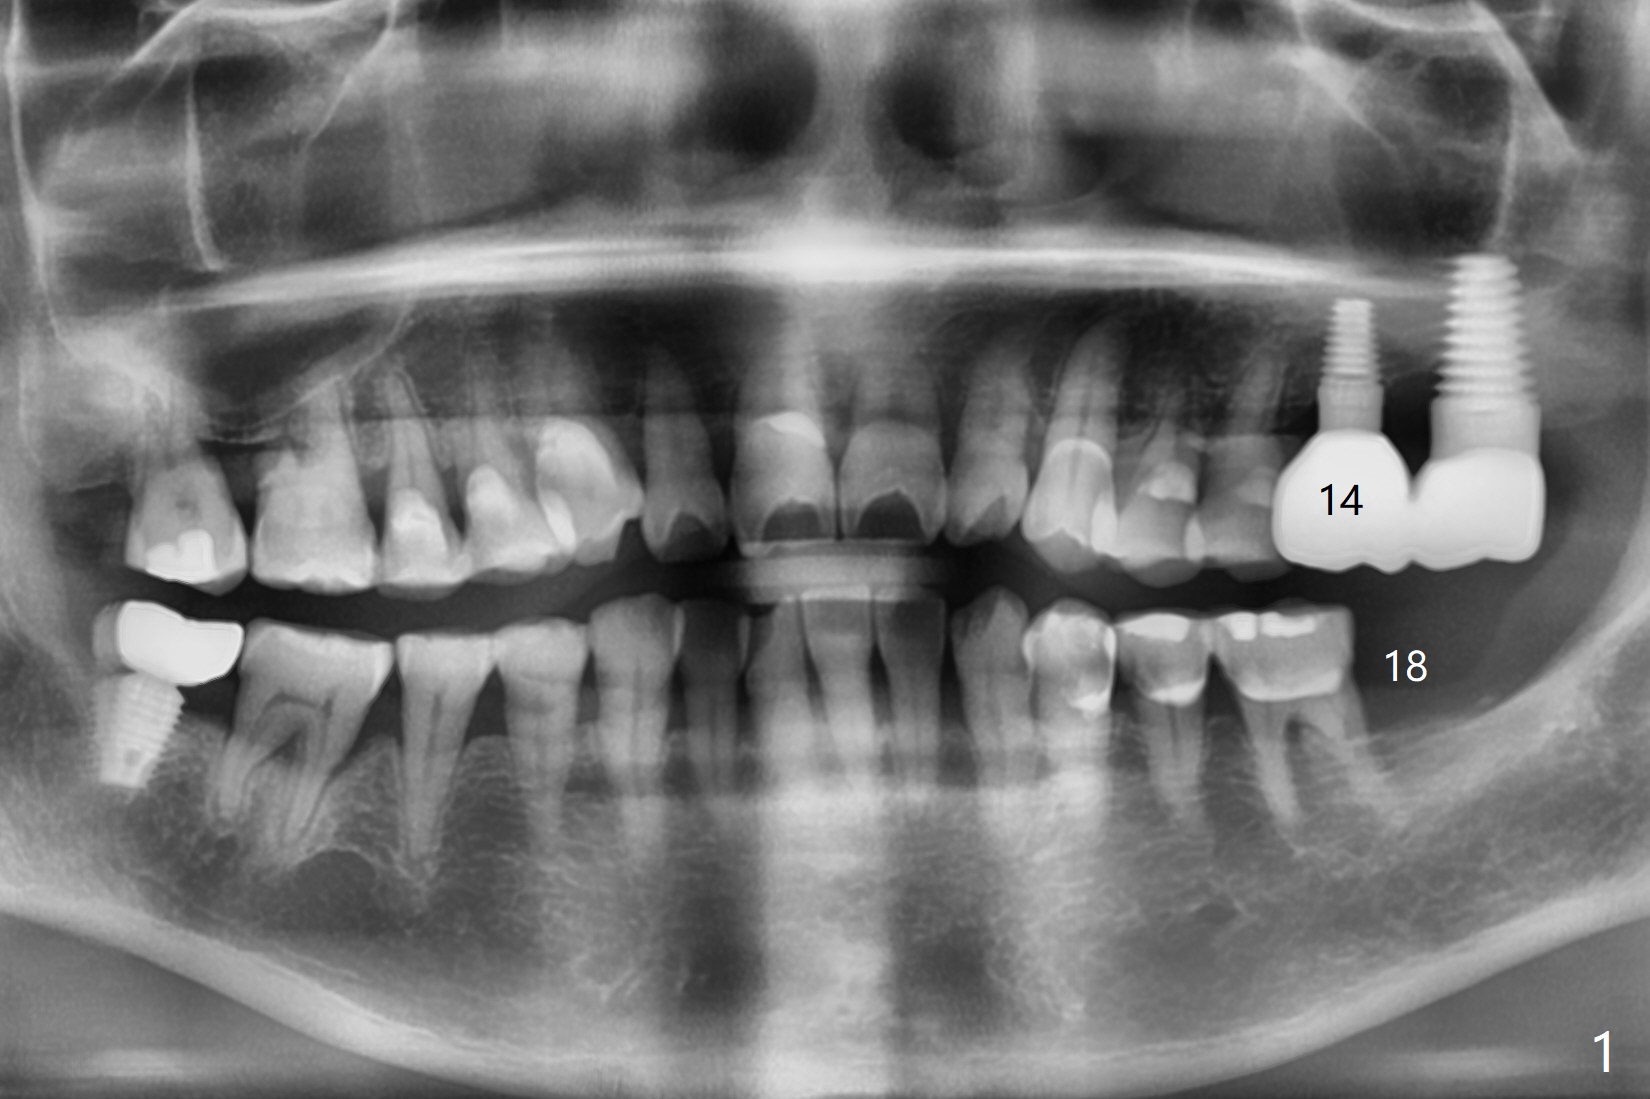

A 62-year-old woman returns for #18 implant with guide 3 months post #14 crown cemen-tation (Fig.1). The implant at #14 was placed free hand after guided osteo-tomy. It appears that its buccal plate is thin (Fig.2). Full guided surgery seems to be nece-ssary.